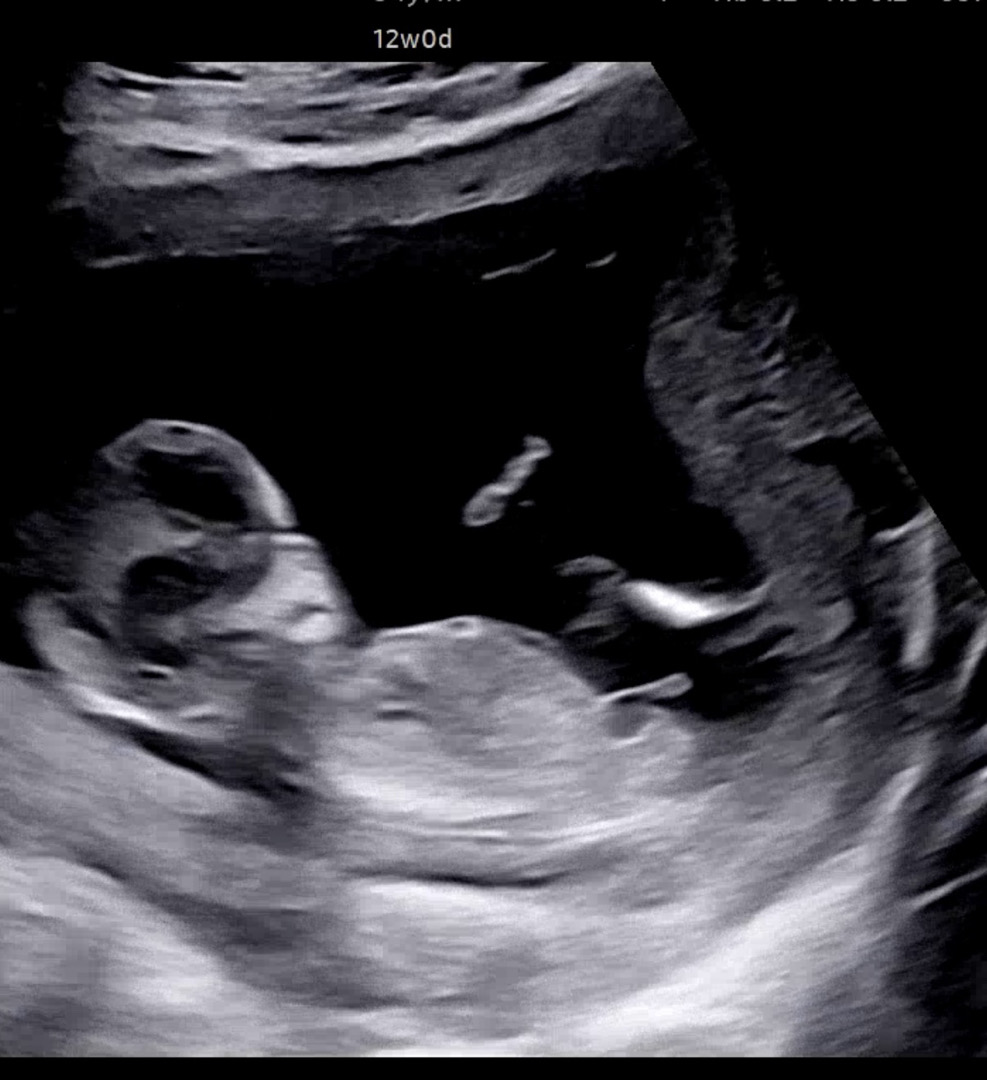

์ด๊ฑฐ ๐ถ๏ธ๋ง๋์? 12์ฃผ ๊ฐ๋๋ฒ๋ด์ฃผ์ธ์

๊ฐ๋๋ฒ ๋ด์ฃผ์ธ์~ ์ ๊ฒ ๊ณ ์ธ๋ง์๊น์???!